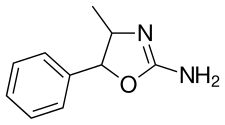

| Formula | C10H12N2O | ||

| Molar mass | 176.219 g·mol−1 | ||

| Chirality | Racemic mixture | ||

4-Methylaminorex (4-MAR, 4-MAX) is a stimulant drug of the 2-amino-5-aryloxazoline group that was first synthesized in 1960 by McNeil Laboratories.[2] It is also known by its street name "U4Euh" ("Euphoria"). It is banned in many countries as a stimulant. 4-Methylaminorex has effects comparable to methamphetamine but with a longer duration.

4-Methylaminorex exists as four stereoisomers : (±)-cis and (±)-trans. The (±)-cis isomers are the form used recreationally.